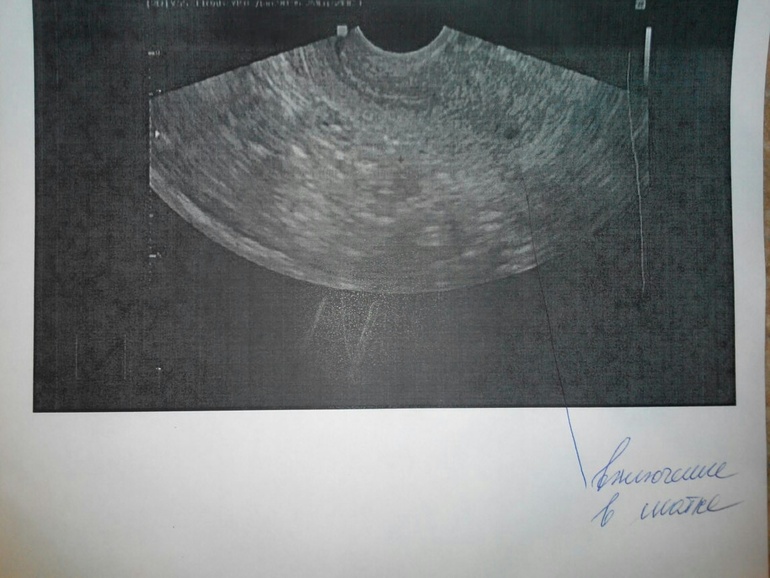

Была на УЗИ..

И я боюсь внематочной. Сказали возможно беременность 2недели. И еще матка маленькая и опущена..